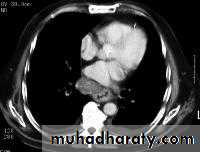

Computed Tomography

Contrast-enhanced CT plays an important role in the1.staging of esophageal carcinoma. to 2.determining the extent of the local tumor; 3.invasion of mediastinal structures; 4.involvement of supra clavicular, mediastinal, or upper abdominal lymph nodes

5. Assessment of the distant metastases

examination should extend from the thoracic inlet through the liver

Routine oral contrast material such as (gastrographine) or a negative intra luminalcontrast medium, such as water.

+/ - IV contrast injection

CT essential in the Dx & staging of the CA

CT finding of esophageal malignancy

1.Eccentric or circumferential wall thickening is greater than 5 mm.

2.Peri-esophageal soft tissue and fat stranding may be demonstrated.

3.A dilated fluid- and debris-filled esophageal lumen is proximal to an obstructing lesion.

4.Aortic invasion .

5.Osophageal CA is often metastatic at the time of presentation ( look for the LN & distal metastasis ) .